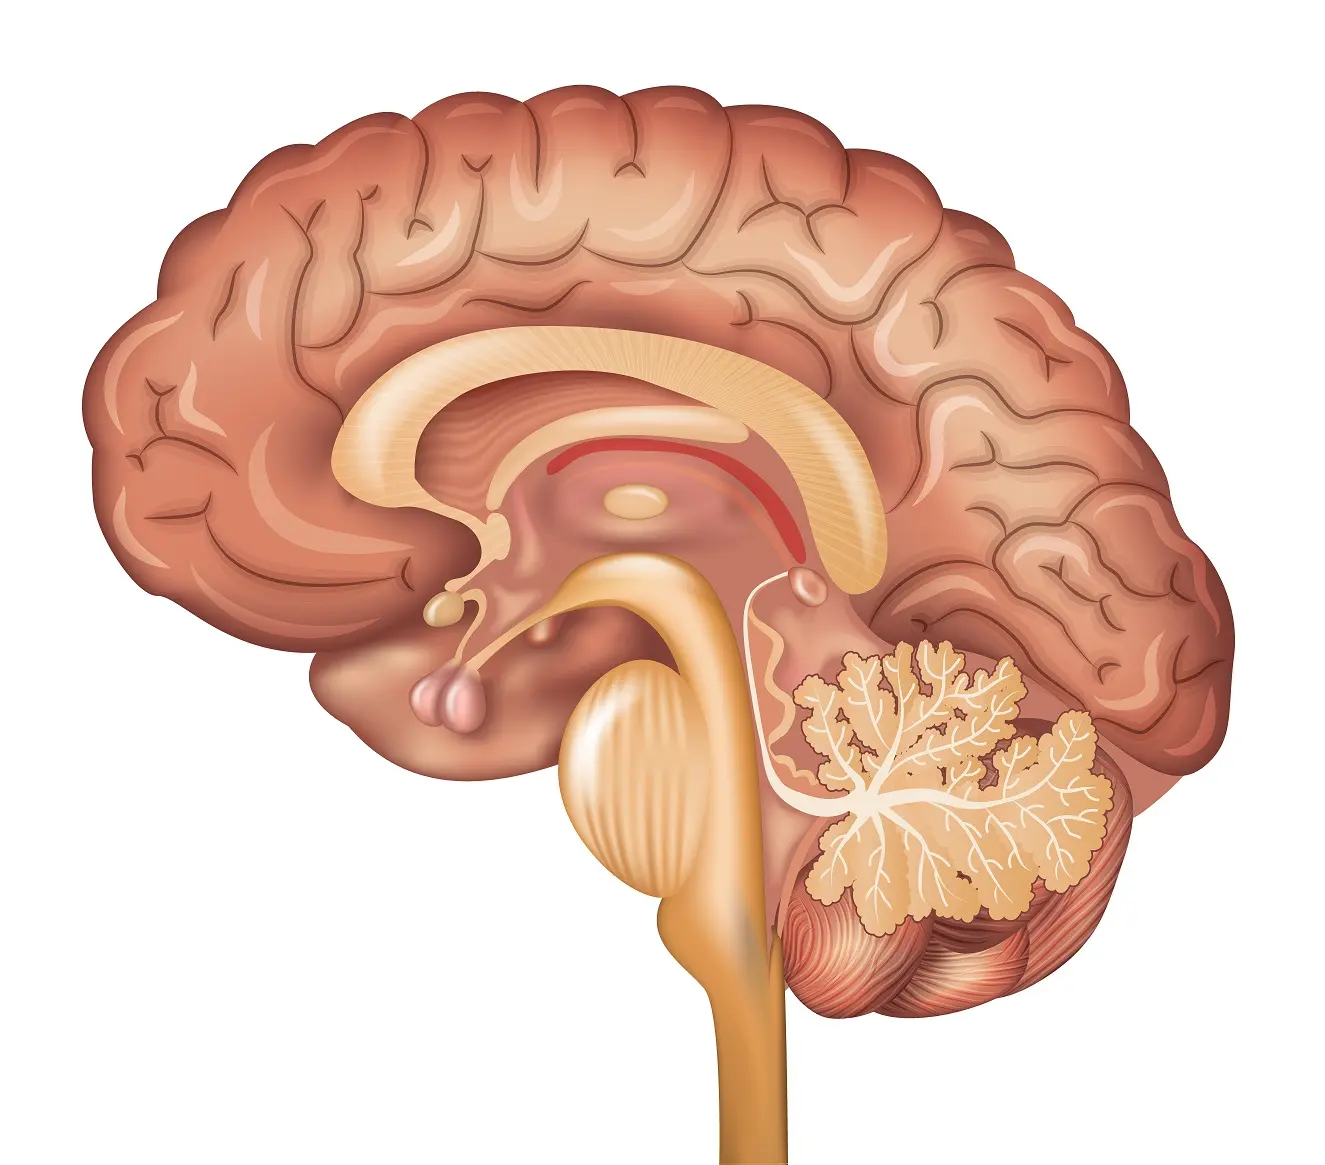

L-theanine is a naturally occurring amino acid found exclusively in tea leaves. [1] Multiple

studies have investigated the effects of l-theanine on the nervous system, especially as its

chemical structure is similar to that of glutamate [4] and in that it can readily cross the

blood-brain barrier. [5] The calming and anxiolytic effect of l-theanine has been well-

documented, meanwhile other studies are investigating its effects on cognitive function,

including learning and memory. [5]

of l-glutamic acid to glutamate receptors in the brain, l-theanine may be able to attenuate activation of the central nervous system. [6] This can lead to a mitigation

Current research has demonstrated that L-theanine exerts effects on the glutaminergic

system, and also increases dopamine activity in animal models. [8] These combined

may be responsible for the cognitive enhancing effect in animal studies, with respect

to learning and memory.

In part of its effects on neurotransmission, l-theanine has also been shown to

have cerebroprotective benefits for the brain: Research has shown that l-theanine

can prevent neuronal cell death after transient cerebral ischemia, which may be

due to its ability to affect glutaminergic pathways. [11] Specifically, l-theanine has

been shown to act on glutamine transporters to inhibit the transport of extracellular

glutamine into neurons. [11] This would mitigate over-excitation responses when